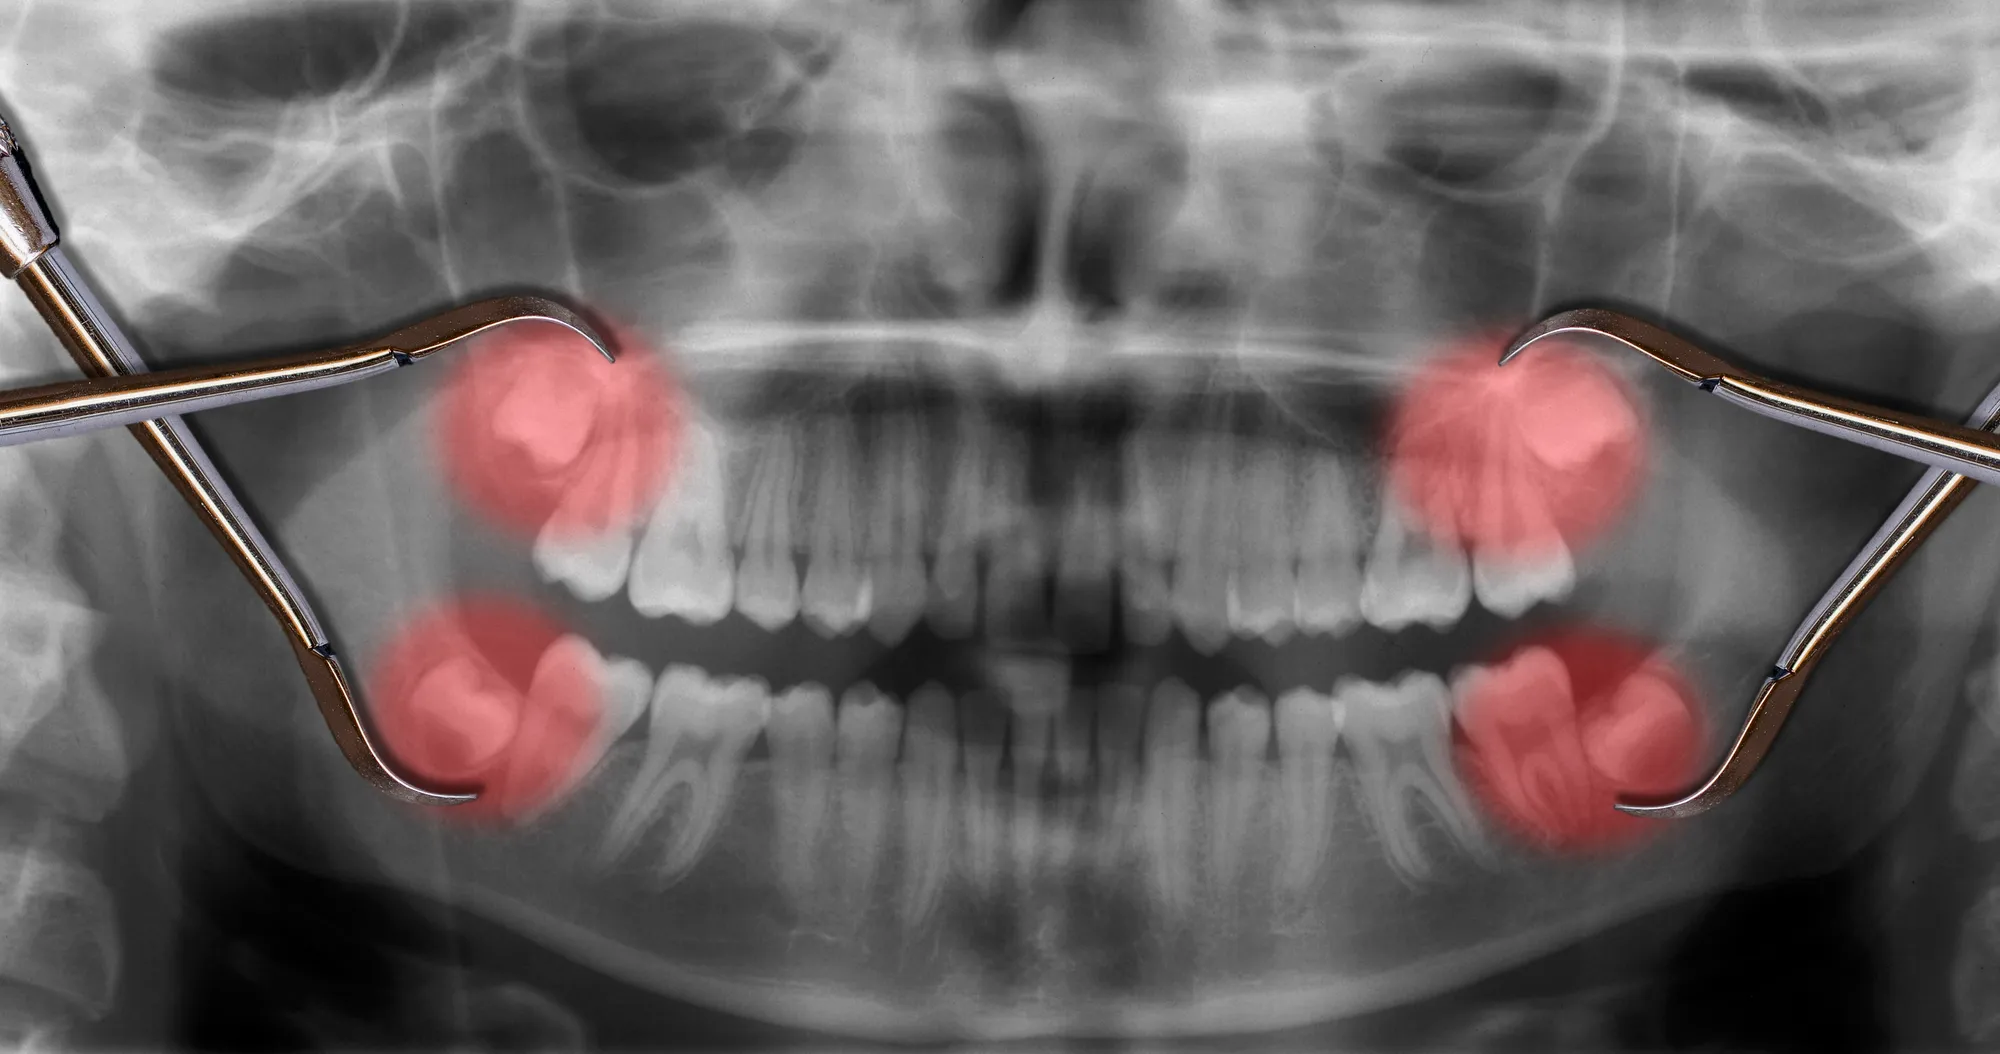

- Impacted teeth, including wisdom teeth

- Surgical Extraction: Used for teeth that are impacted, broken, or not fully erupted. The dentist makes a small opening in the gum and, when needed, removes the tooth in sections.